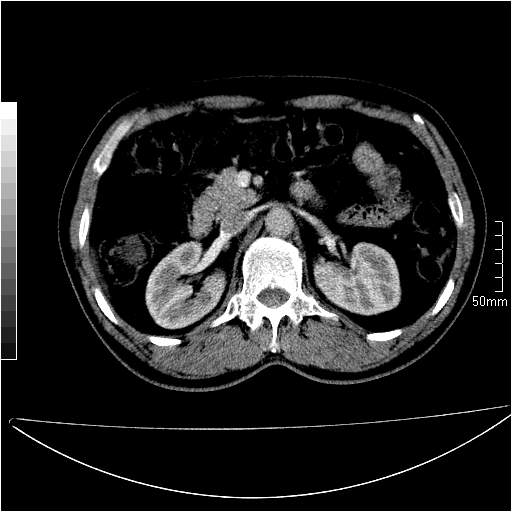

男性,54岁,皮肤黄染,搔痒一周余.b超示肝左叶回声异常.初步诊断1胆总管下段结石2胆囊结石伴慢性胆囊炎请各位战友帮忙看一下肝脏多发低密度如何解释恰当.增强效果不是很好.请大家见谅.

胆总管及肝内胆管扩张,考虑是结石!但,肝内的低密度区增强不明,可能是肝ca,因为肝ca在增强时呈快进快出.另年胆总管扩张原因,可以考虑一下是不是,胆管ca.再次要考虑肝内的低密度是否为海绵状血管瘤所致!

首先,胆总管下端结石梗阻伴肝内胆管扩张可确定。

其次,增强动脉期肝静脉显影,肝实质密度不均。——此为右心功能不全引起肝淤血的表现。

另外,肝八段低密度占位,呈多灶性,考虑肝脓肿或肝癌可能,(图像质量欠佳)建议进一步检查。

由于胆囊窝内结构显示不清,肝脏病灶又邻近胆囊窝首先考虑胆囊癌肝受侵犯。而后因肝脏病灶强化有渐进改变,且相邻胆管扩张,故考虑肝胆管细胞癌待排。

左肝胆管细胞癌。

胆总管下端结石。